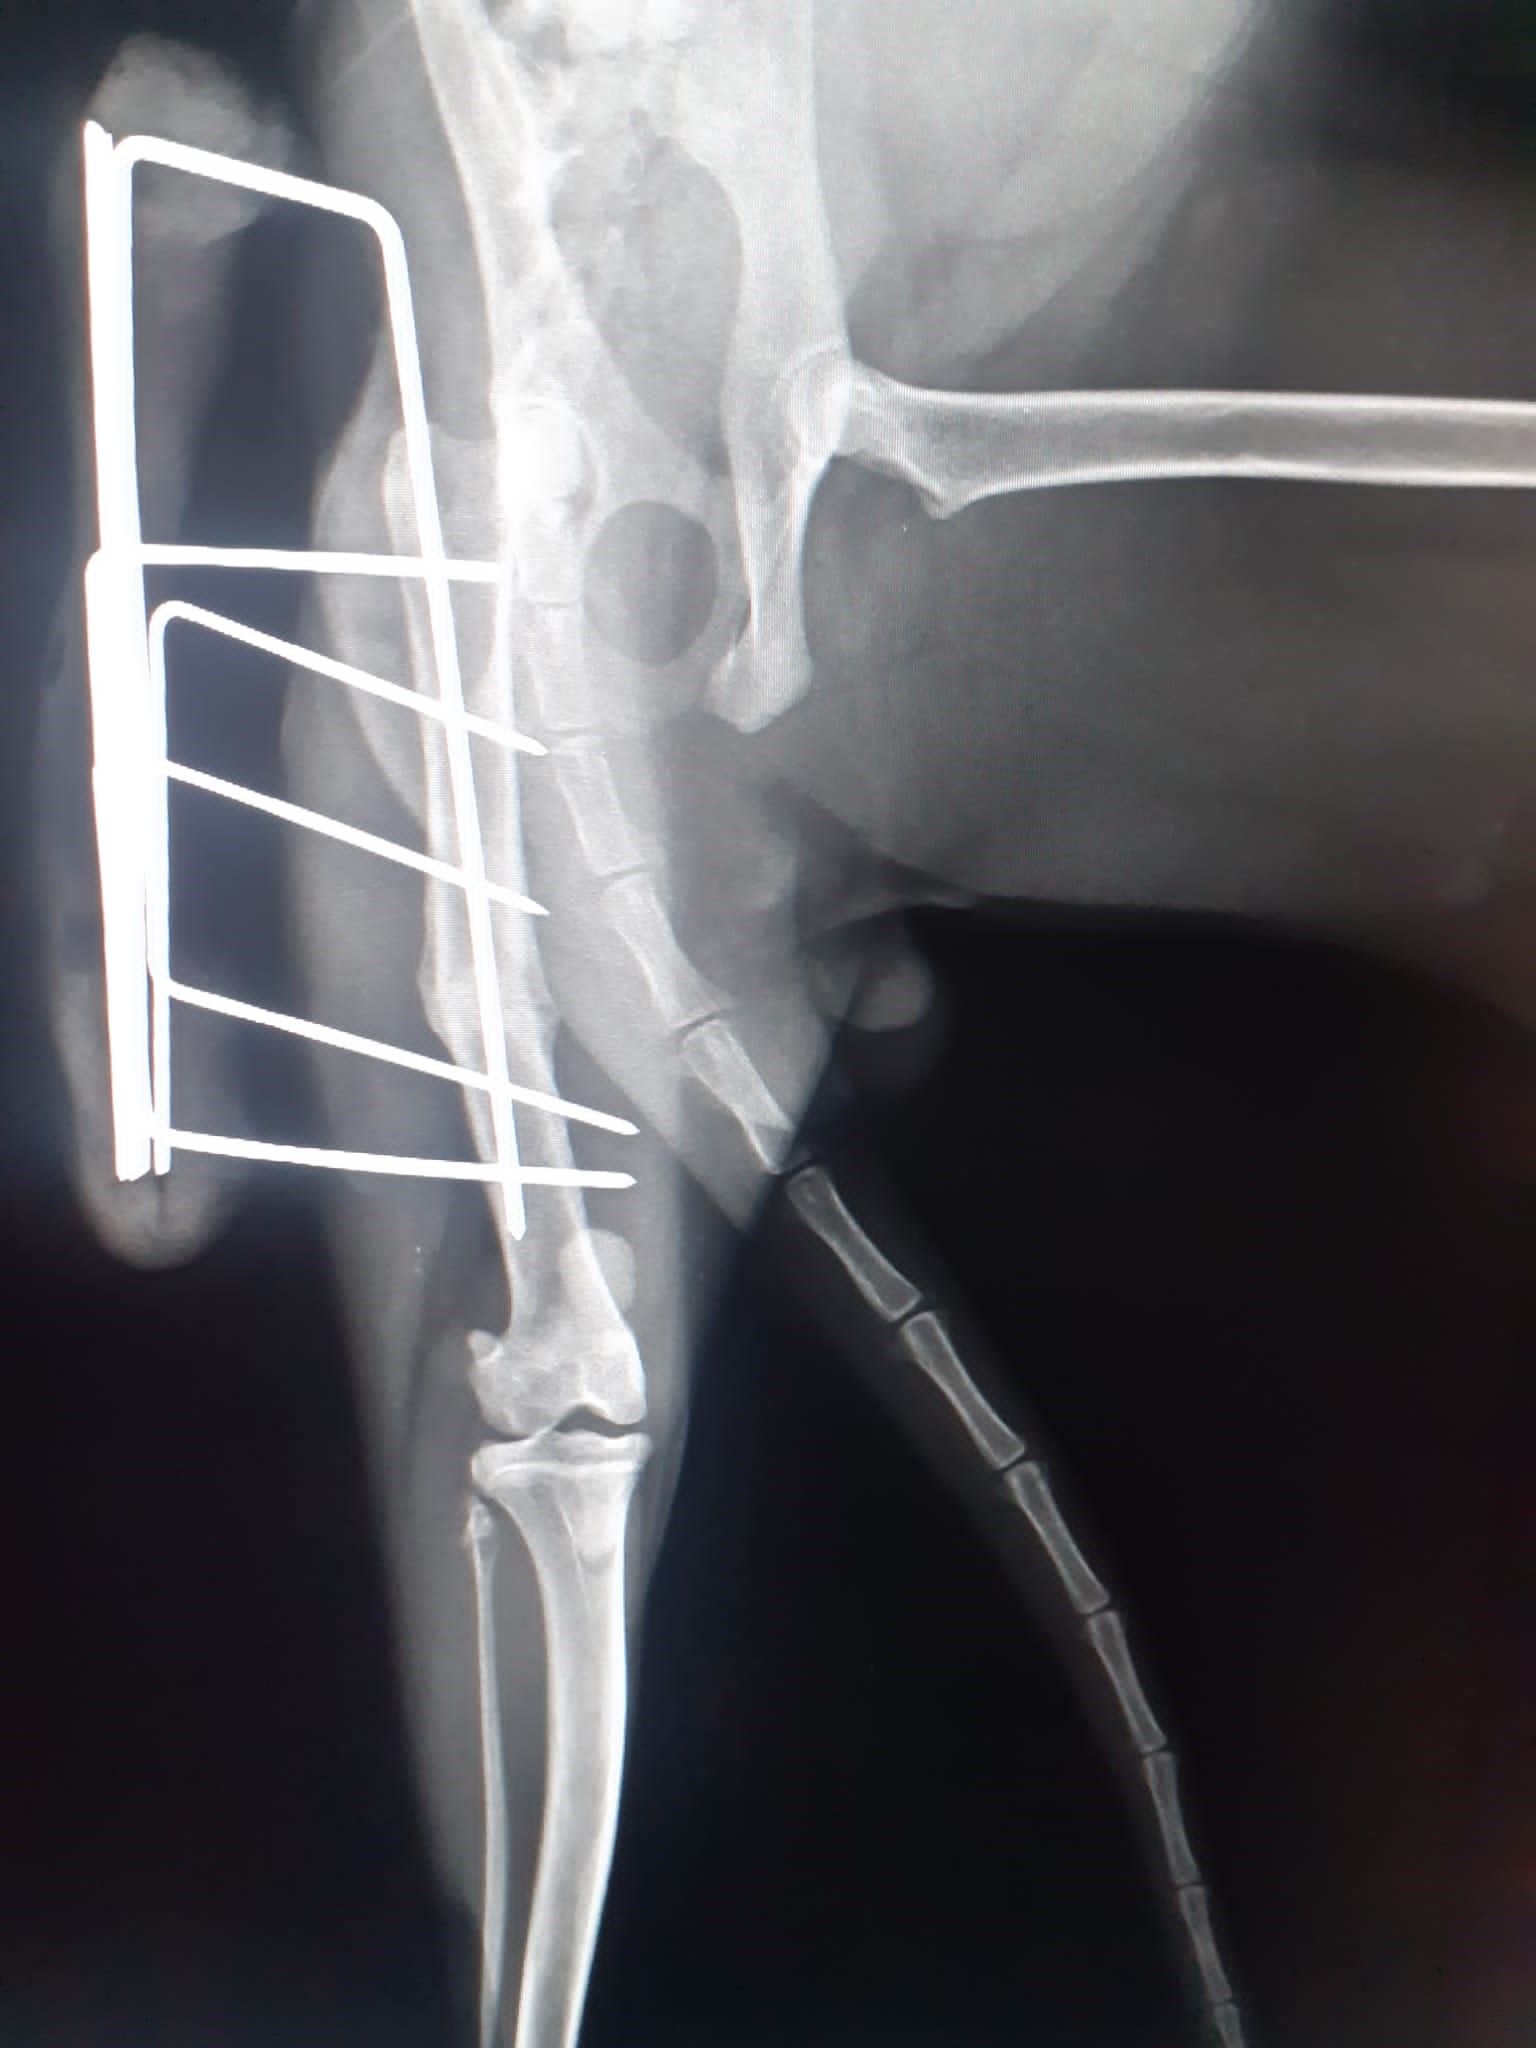

Alla clinica veterinaria Città di Catanzaro siamo a disposizione per eseguire controlli radiografici specifici per la diagnosi di alcune tra le più diffuse malattie ortopediche che affliggono molte razze canine, soprattutto nella fase della crescita.

Con sicurezza ed efficacia, i nostri esperti di ortopedia veterinaria sono capaci di prevenire e curare tutti i tipi di problematiche relative all'apparato muscolo scheletrico, come la displasia dell’anca e del gomito.

In più, la nostra équipe si compone di esperti traumatologi che si dedicano alla diagnosi, al trattamento e alla prevenzione di un ampio spettro di patologie dell'apparato locomotore.

Infine, grazie alla chirurgia ortopedica, è possibile velocizzare la guarigione di tutti quegli animali che hanno subito fratture ossee in seguito a qualsiasi tipologia di incidente.